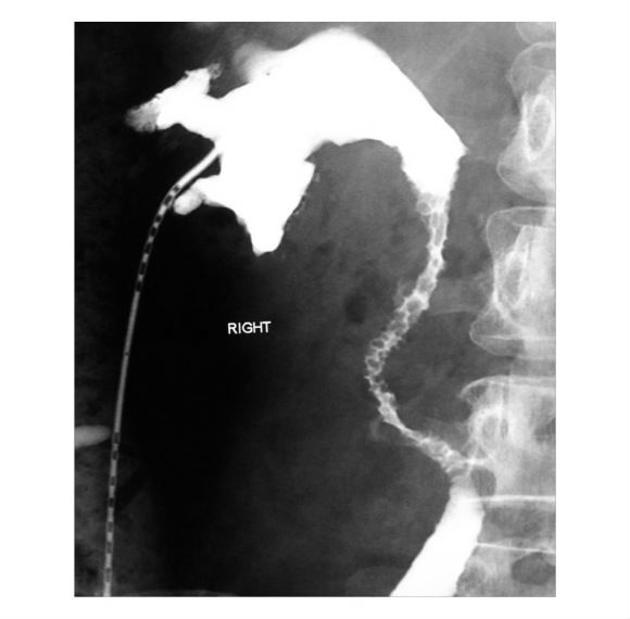

ureteritis cystica